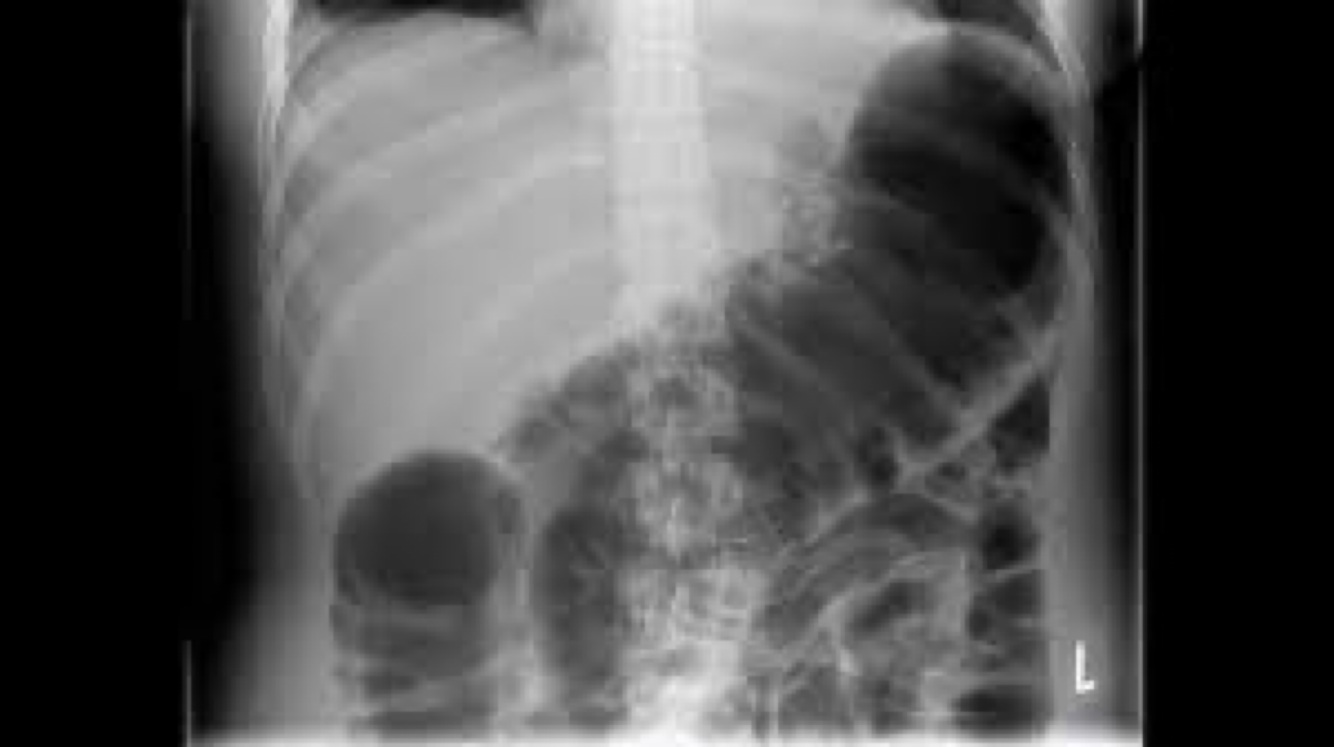

What disease has a stacked coin x- ray?

A

Intussusception

Not at all

2